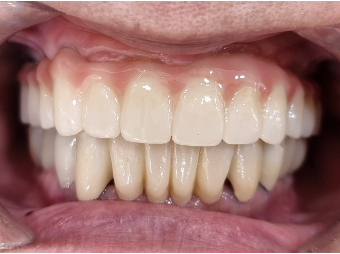

디지털 풀아치 임플란트(상악) (73세 남성)

디지털 풀아치 임플란트(상악) & 전체 임플란트(하악) (64세 여성)